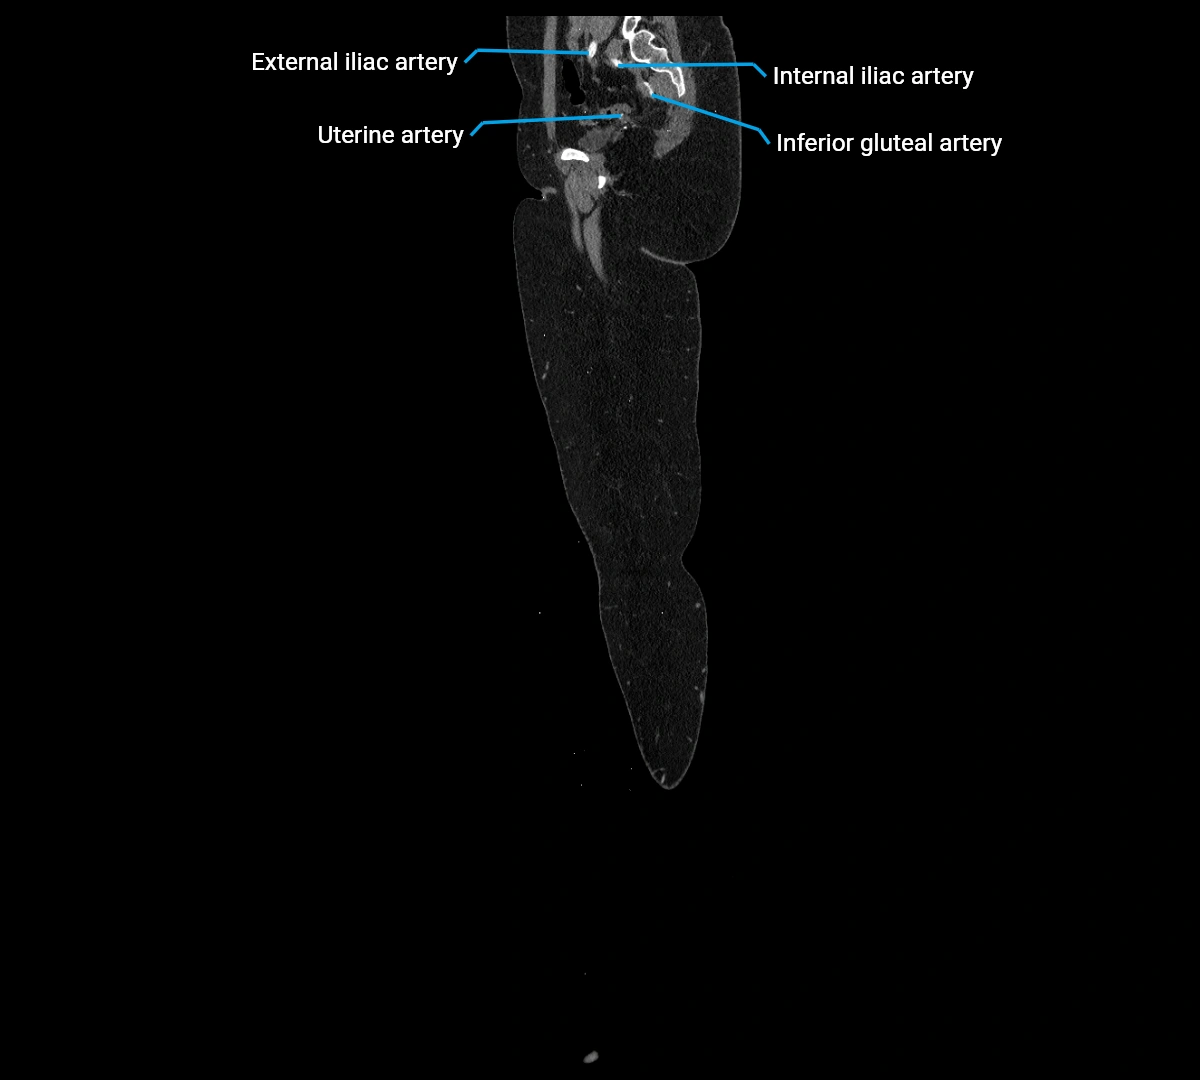

Contrast-enhanced CT (CTA):

• Gold standard for abdominal aortic imaging

• Provides excellent detail of lumen, wall, aneurysm, thrombus, and branch vessels

• Multiplanar and 3D reconstructions help in aneurysm measurement, stent graft planning, and dissection evaluation

• Detects acute rupture, traumatic injury, or occlusion with high sensitivity